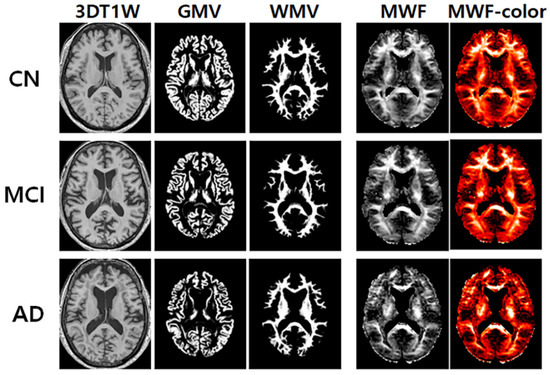

Figure 1 shows the representative maps of the apparent MWF with and without using color, 3D T1W, GMV, and WMV obtained from one elderly CN participant (72-year-old female), one MCI (72-year-old female) participant, and one AD (73-year-old female) participant. The apparent MWF signal was nicely depicted around the white matter areas. A gross signal drop in the apparent MWF signal was observed in the AD group compared to the CN group in the white matter.

Figure 1.

Representative maps of the three-dimensional (3D) T1-weighted (T1W), gray matter volume (GMV), white matter volume (WMV), and apparent myelin water fraction (MWF) with and without color code.